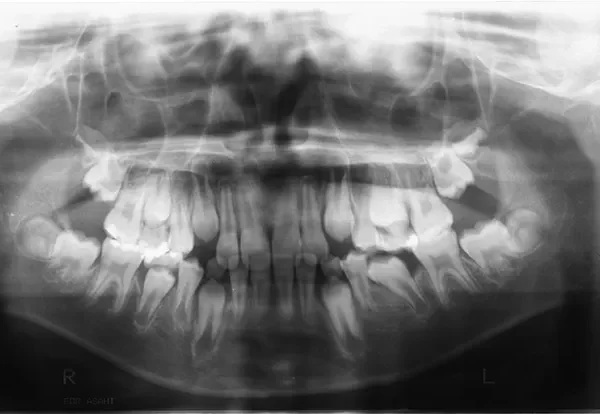

• 治療終了後

治療終了後

下の歯は永久歯の生えるスペースがないので、オリジナル矯正装置で受け口を治して、永久歯の生えるスペースを作りました。

治療回数19回、2年5ヶ月の治療期間で矯正治療を終了しました。

主訴が改善され、ご満足頂きました。